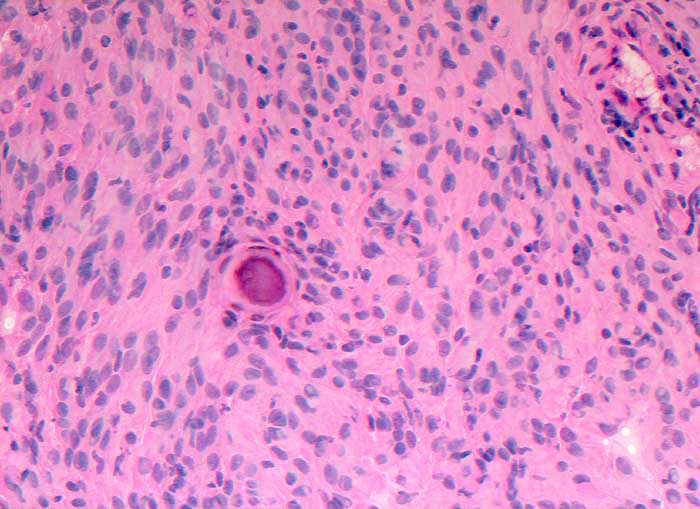

Meningeom

benigner Tumor

Rückenmark

Nervensystem

Im Schnellschnitt sind psammomatöse Verkalkungen und meningotheliale Zellen ohne Atypien erkennbar.

Spinaler Tumor Th 12.

Zytologische Diagnose: Meningeom. Am ehesten handelt es sich um einen transitionalen Typ mit häufigem Nachweis von Wirbelbildungen und Psammomkörperchen.

Schnellschnitt

200